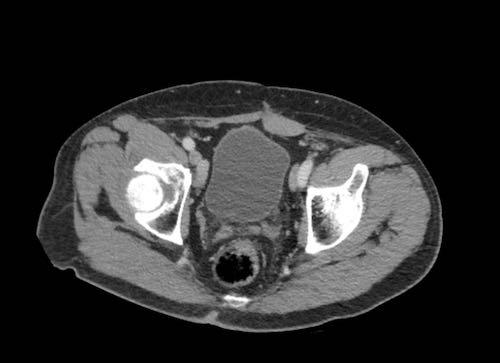

Ca lâm sàng 2

Cuộn qua các lát cắt.

Bạn có thể phát hiện tất cả các tổn thương cấy ghép phúc mạc không?